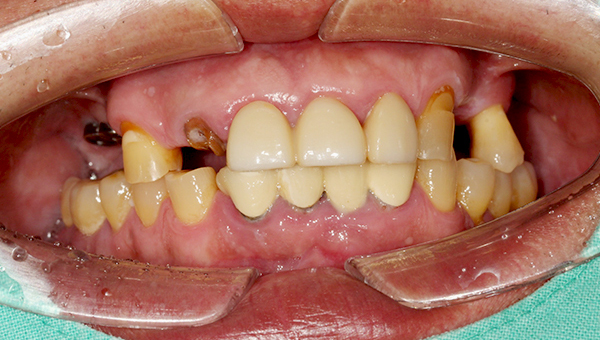

김*현 임플란트 시술 사례

구치부/전치부 임플란트

2025.06.10

치료 전